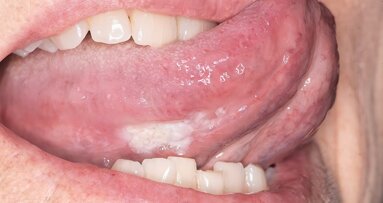

Ciro Dantes Soares, et al19 presentan las características clínicas y microscópicas de las lesiones orales y rojizas orales que ocurrieron en un paciente masculino de 42 años positivo para SARS-Cov-2 confirmado por reacción en cadena de la polimerasa (PCR).

Comentan que el enfermo se quejó de una ulceración dolorosa en la mucosa bucal que fue biopsiada. El examen oral mostró, además de la lesión ulcerada, múltiples máculas rojizas de diferentes tamaños esparcidas a lo largo del paladar duro, la lengua y los labios Después de 3 semanas de seguimiento, las lesiones presentaron remisión completa.

Describen las características microscópicas de las lesiones orales: epitelio que demuestra vacuolización y hemorragia en la porción superficial de la lámina propia, con vasos hiperémicos. Infiltración linfocítica en el tejido conectivo y trombos de diferentes tamaños. Expresión positiva de CD34 en trombos de pequeños vasos. Trombos más grandes con una cantidad variable de fibrina y células endoteliales positivas para CD34.

En la lámina propia, un infiltrado inflamatorio crónico difuso se asoció con áreas focales de necrosis y hemorragia. Los pequeños vasos visibles superficiales y profundos fueron borrados por trombos evidentes.

Los trombos pequeños parecían estar compuestos principalmente por células endoteliales, mientras que los más grandes estaban compuestos por fibrina y células endoteliales.

Las glándulas salivales menores adyacentes exhibieron una intensa infiltración linfocítica, principalmente positiva para CD3 y algunas de estas células también se encontraron en la capa basal del epitelio. Las reacciones inmunohistoquímicas contra HHV-1, HHV-2, CMV, treponema pallidum y EBV por hibridación in situ fueron negativas. Teniendo en cuenta las características clínicas y microscópicas, se sugirió que el paciente presentaba lesiones que podrían asociarse con la enfermedad de Covid-19.